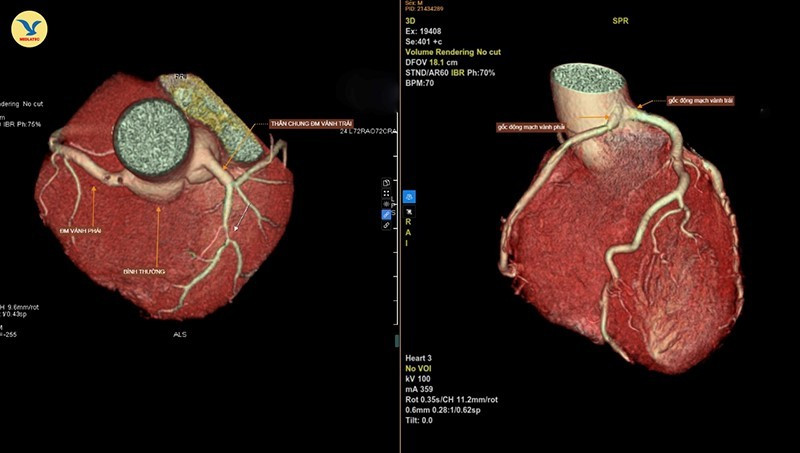

Hình ảnh chụp CTA 3D. Bên trái là động mạch vành bình thường. Bên phải là hình ảnh hai nhánh động mạch vành trái và phải xuất phát chung từ một gốc

Kết quả chụp cho thấy, một bất thường bẩm sinh hiếm gặp của động mạch vành nuôi cơ tim: bệnh động mạch vành đơn (Single coronary artery) - type LII-B.

Với bất thường này, hai nhánh động mạch vành trái và động mạch vành phải của bệnh nhân xuất phát chung từ một gốc thay vì xuất phát ở hai vị trí riêng biệt, đồng thời bị kẹp giữa thân động mạch phổi và gốc động mạch chủ, khiến cho chúng bị hẹp bẩm sinh. Cụ thể ở ca bệnh này, nhánh động mạch vành phải bị hẹp khoảng 45% đường kính.

Đây là một dị tật bẩm sinh hiếm, chỉ gặp dưới 0,05% dân số. Trong đó, type LII-B (phân loại Lipton) là biến thể có đường đi nguy cơ cao, khi động mạch vành phải xuất phát từ xoang Valsalva trái và chạy giữa động mạch chủ - thân động mạch phổi, dễ gây thiếu máu cơ tim và đột tử, đặc biệt khi gắng sức.